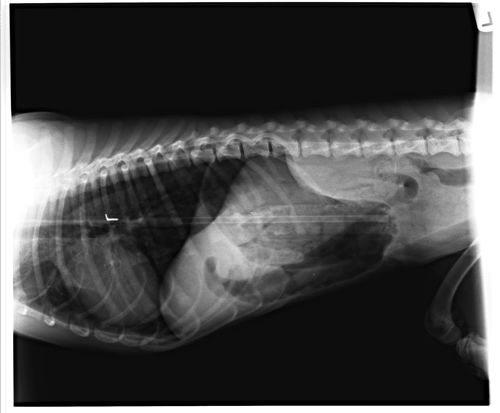

Os veterinários, para participar do concurso, utilizam radiografias que foram tiradas em clínicas para mostrar toda a coleção bizarra de coisas que acabaram virando jantar de bichos. Existem exemplos que vão desde controles de Playstation, caixas de cigarro, uma corrente, uma faca de caça com uma bainha, entre outros.

No quesito de comprimento, um cão de Nova Jérsei engoliu um coçador de costas com mais de 35 cm de comprimento.

Uma outra curiosidade foi uma cobra construtora, que era criada por outra família e foi levada ao veterinário, quando eles descobriram que ela havia engolido o papagaio da casa.